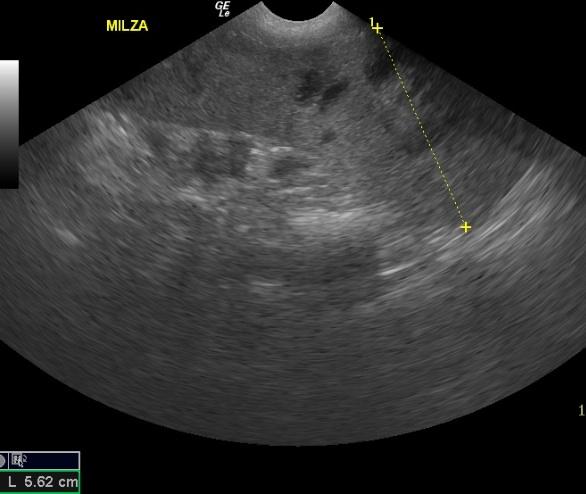

The spleen was heterogenous with mixed hypoechoic nodular or cavitated lesions and areas of capsular expansion. No evidence of rupture was noted. However, a mass is present at the caudal splenic body.

SplenicabcessSplenicabcessSplenicabcess